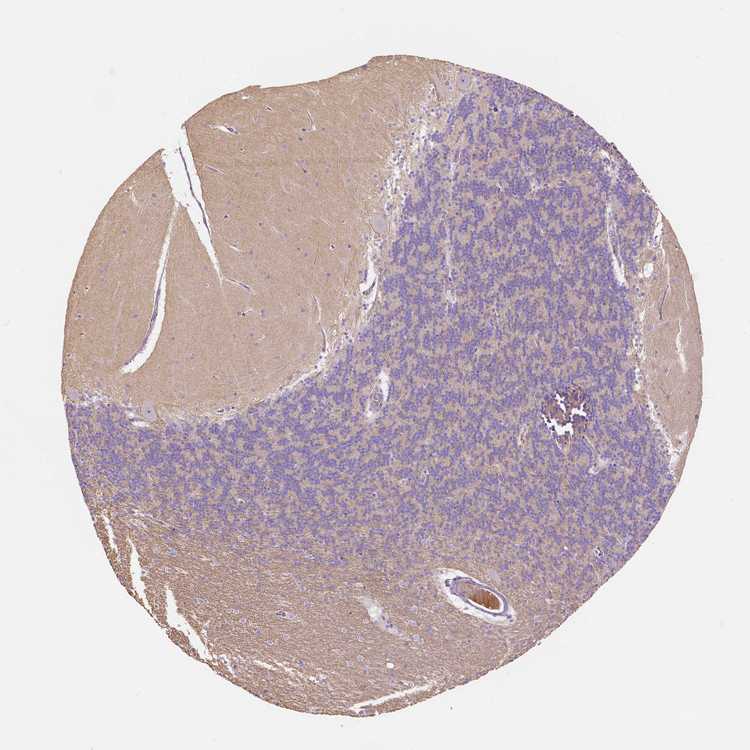

CEREBELLUM - Antibody stainingi

Antibody staining in the annotated cell types in the current human tissue is reported as not detected, low, medium, or high, based on conventional immunohistochemistry profiling in selected tissues. This score is based on the combination of the staining intensity and fraction of stained cells.

Each image is clickable and will lead to virtual microscopy that enables deeper exploration of all samples and also displays staining intensity scores, fraction scores and subcellular localization as well as patient and tissue information for each sample.

Antibody HPA012612

Bergmann glia - cytoplasm/membrane Not detected

Bergmann glia - nucleus Not detected

GLUC cells - cytoplasm/membrane Not detected

GLUC cells - nucleus Not detected

Purkinje cells - cytoplasm/membrane Not detected

Purkinje cells - dendrites Not detected

Purkinje cells - nucleus Not detected

Granular cells - cytoplasm/membrane Not detected

Granular cells - nucleus Not detected

Molecular layer - neuropil Low

Molecular layer cells - cytoplasm/membrane Not detected

Molecular layer cells - nucleus Not detected

Processes in granular layer Medium

Processes in molecular layer Not detected

Processes in white matter Medium

Synaptic glomeruli - capsule Not detected

Synaptic glomeruli - core Not detected

White matter cells - cytoplasm/membrane Not detected

White matter cells - nucleus Not detected